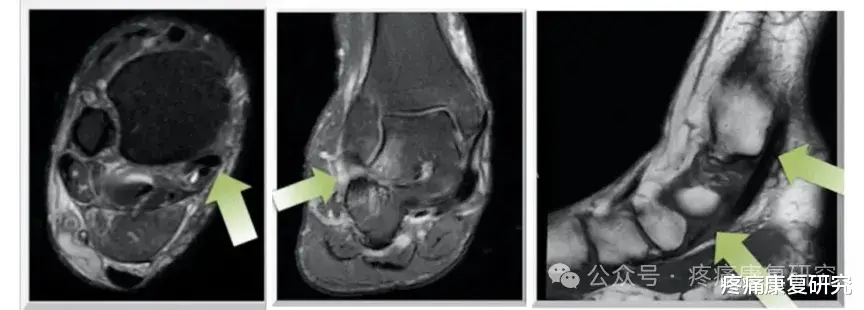

2. 影像学检查(明确病情)

① 超声:快速便捷,筛查肌腱撕裂、增厚、积液;

② MRI:准确性高,明确肌腱退变、撕裂程度及周围软组织损伤;

③ X线:观察骨骼力线,判断扁平足、踝关节炎等继发改变。